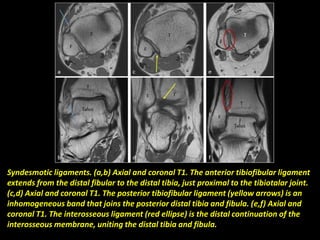

Syndesmotic ligaments. (a,b) Axial and coronal T1. The anterior tibiofibular ligament

extends from the distal fibular to the distal tibia, just proximal to the tibiotalar joint.

(c,d) Axial and coronal T1. The posterior tibiofibular ligament (yellow arrows) is an

inhomogeneous band that joins the posterior distal tibia and fibula. (e,f) Axial and

coronal T1. The interosseous ligament (red ellipse) is the distal continuation of the

interosseous membrane, uniting the distal tibia and fibula.